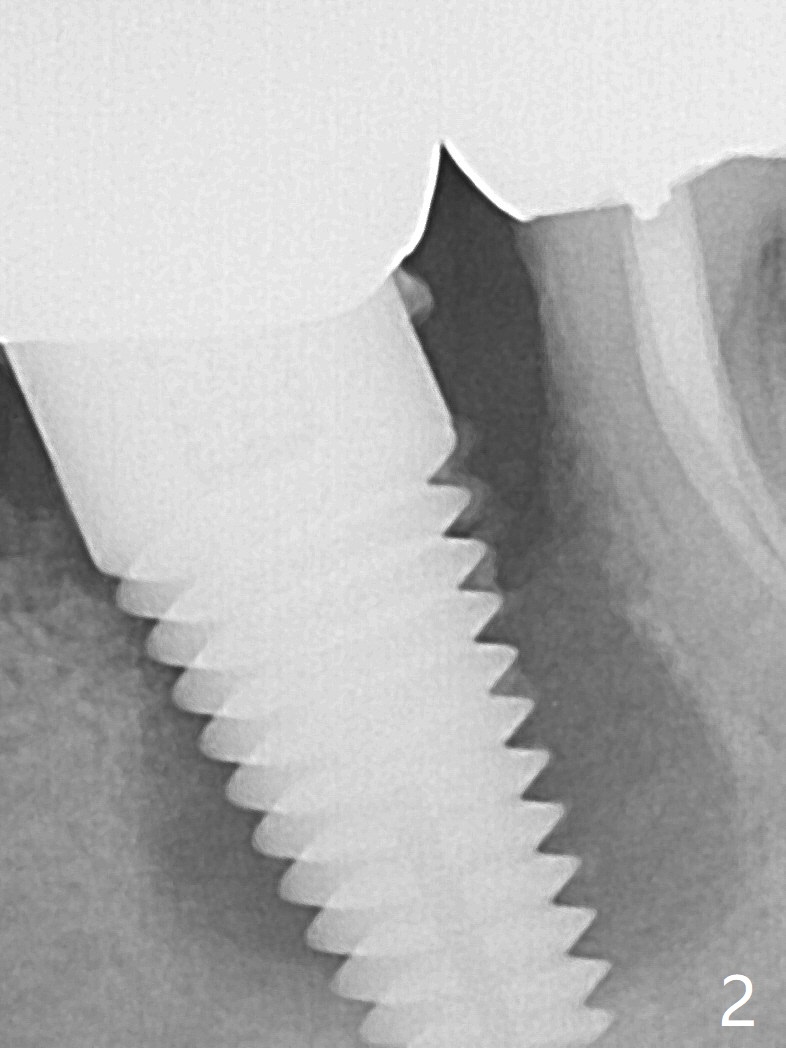

There is calculus formation in the threads of the implant removed (Fig.1), as related to bone loss (Fig.2). Sticky bone is placed, followed by 2 pieces of PRF membranes, 4-0 PGA sutures (Fig.3) and periodontal dressing.